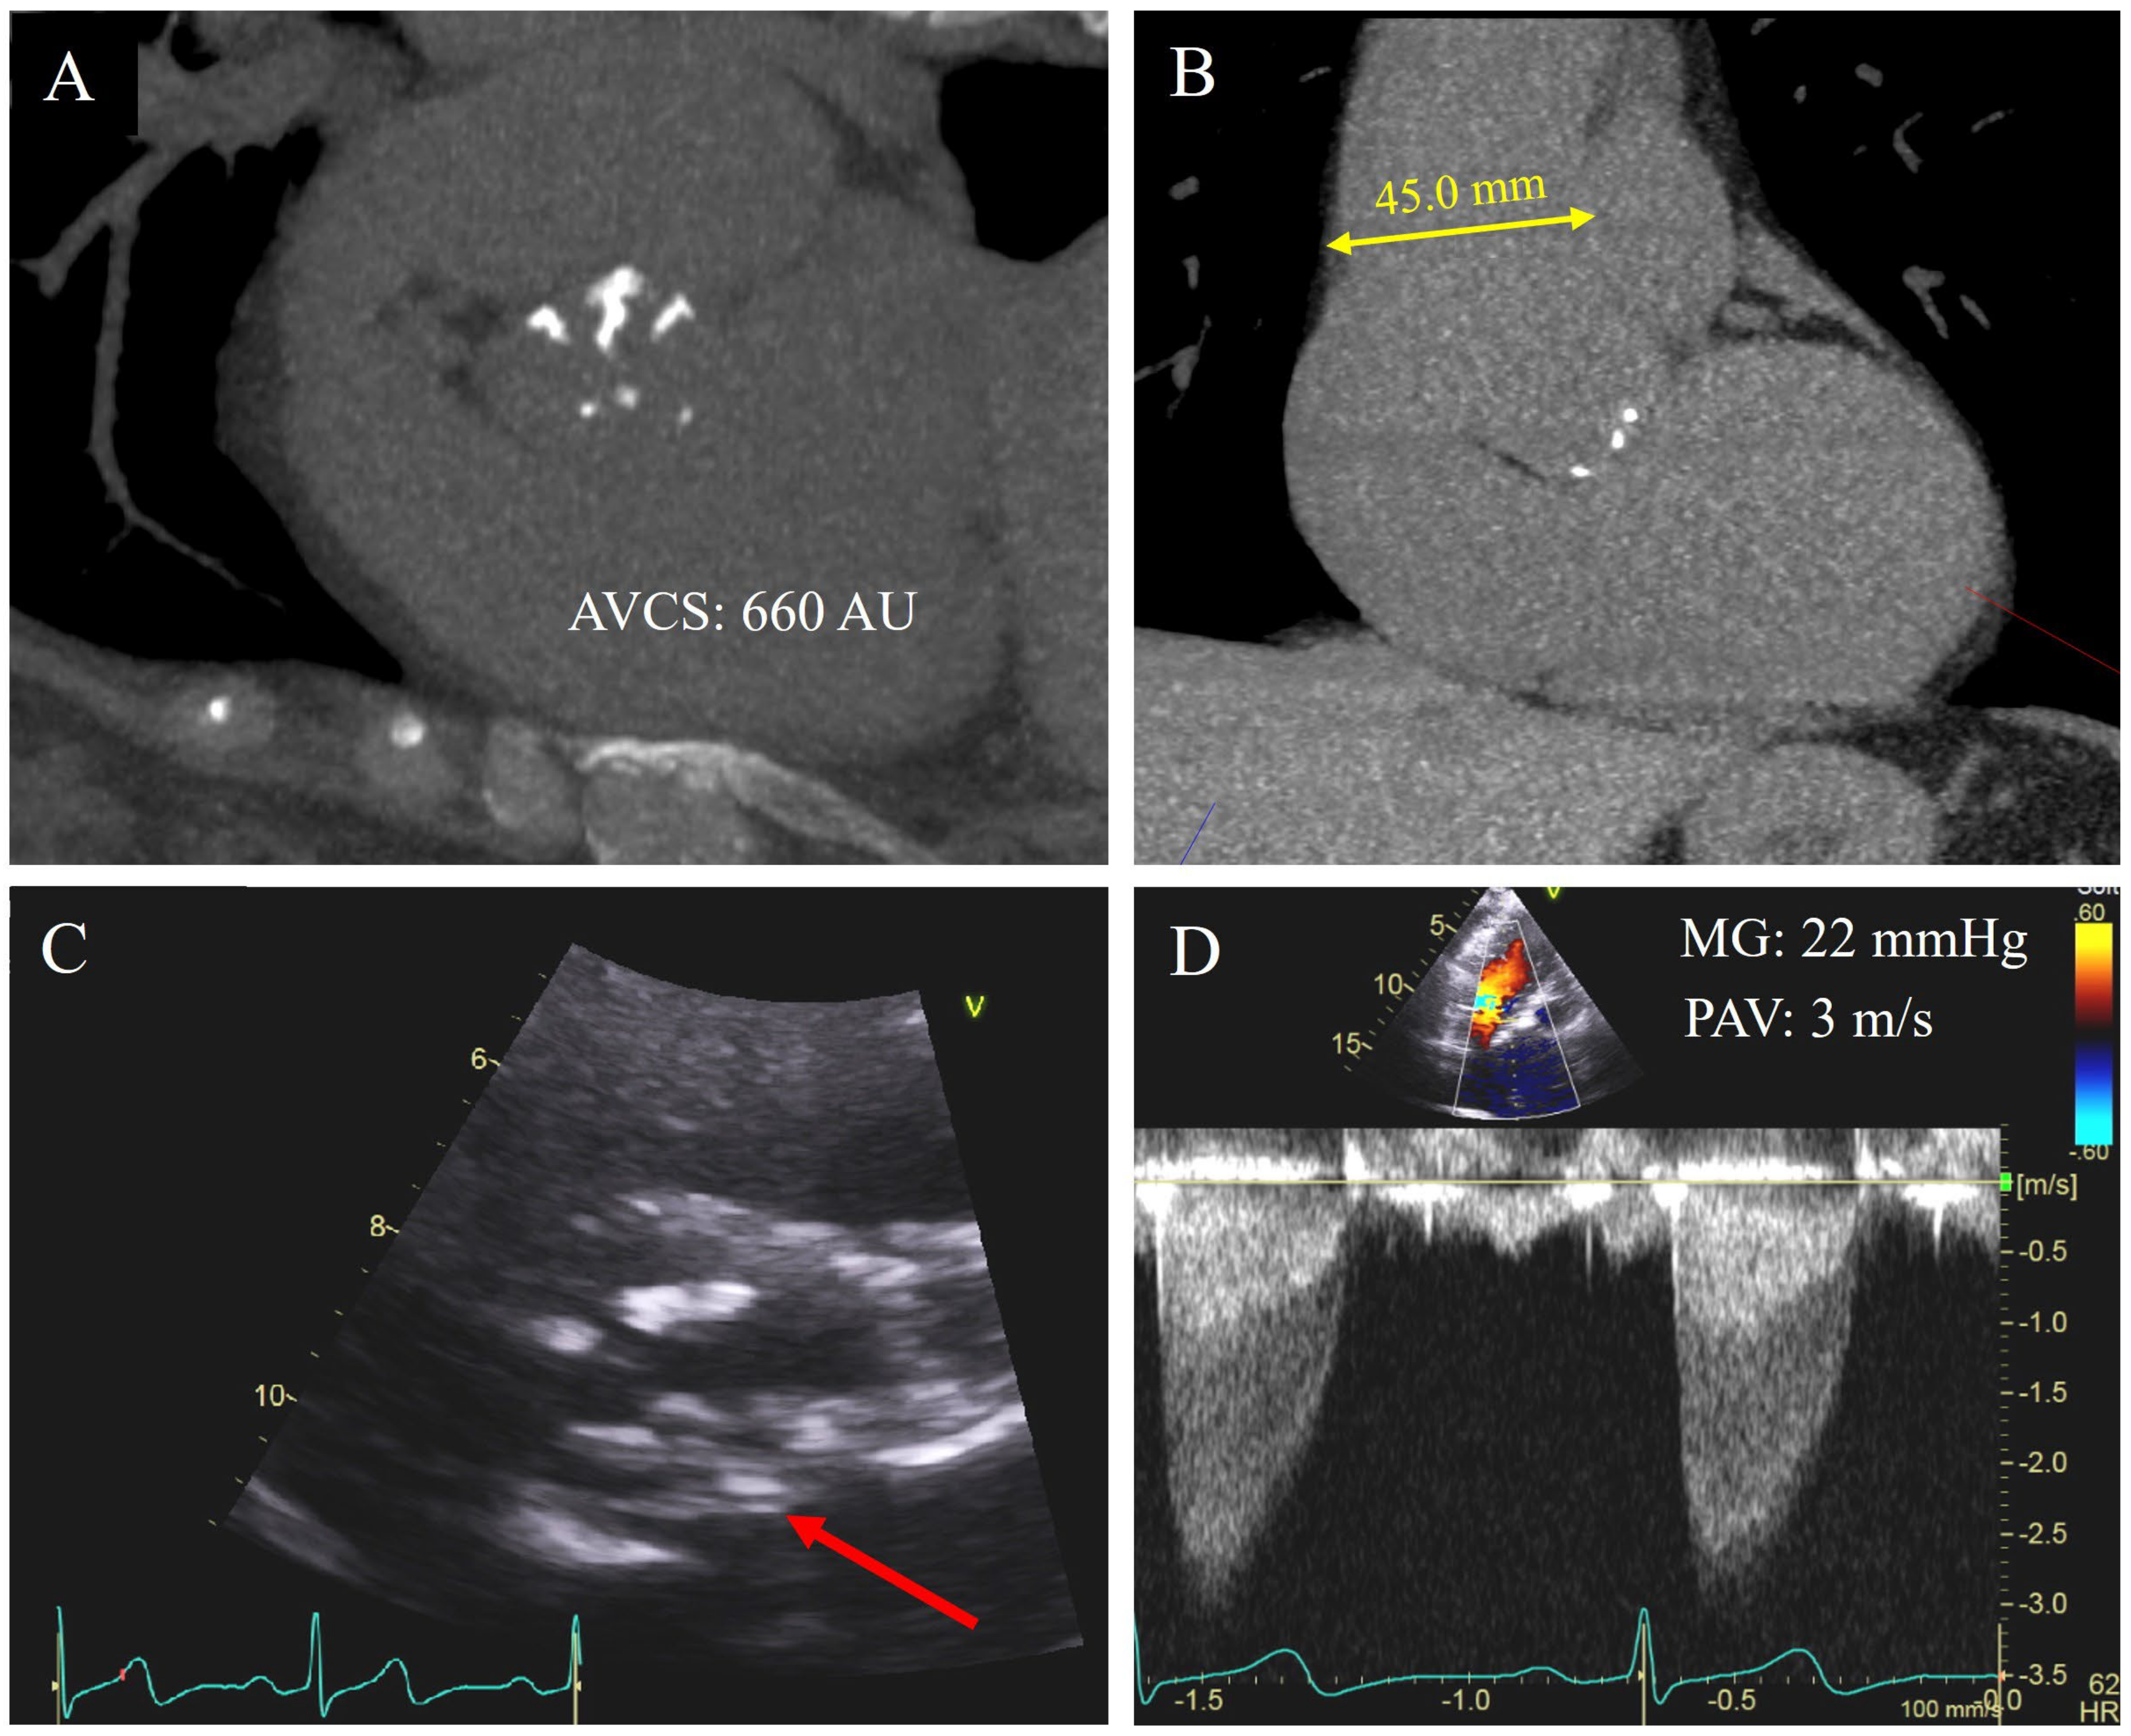

| Moderate: PAV 3.0–3.9 m/s MG 20–39 mmHg | SAVR if undergoing other cardiac surgery | |||